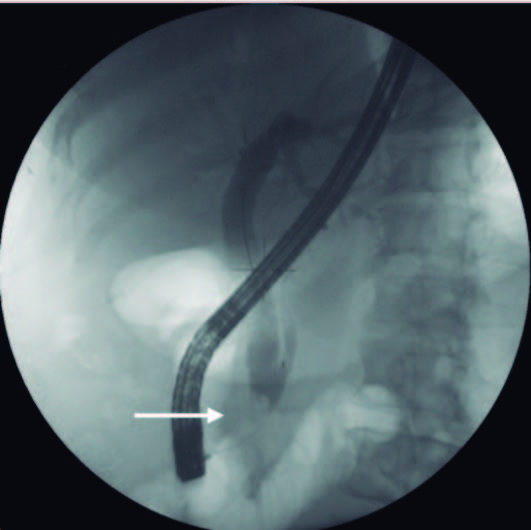

Em 19/02/2020 faz colangiopancreatografia retrógrada endoscópica (CPRE): “VBP muito dilatada com imagens de subtração compatíveis com cálculos. Realizada esfincterotomia endoscópica ampla sem intercorrências. Com recurso a balão de Fogarty extração de pus e abundante quantidade de material litiásico, com vários cálculos, o maior com 17 mm (Fig. 3).